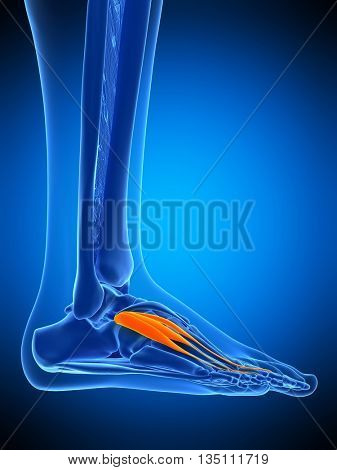

Extensor